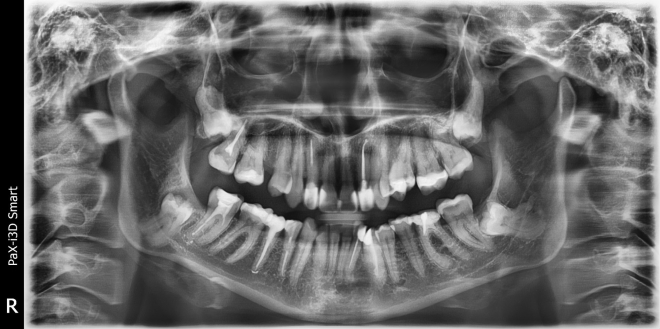

• Діагностика. 6 діагнозів.

• Класифікації за рівнем складності

• Техніки видалення зубів особливості планування від розрізу до останнього шва